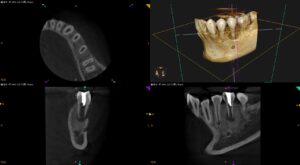

左下奥歯が死ぬほど痛くて子供が夜も寝れない…急化Perに対する対応方法と#20 Regenerative therapy 1回法

紹介患者さんの治療。 主訴は、 左下奥歯が死ぬほど痛くて子供が夜も寝れない… である。 この患者さんの主訴というよりは、この患者さんの親御さんの主訴と言ってもいいだろう。 歯が痛くてとにかく子供を寝かしつけることもできな … 続きを読む 左下奥歯が死ぬほど痛くて子供が夜も寝れない…急化Perに対する対応方法と#20 Regenerative therapy 1回法